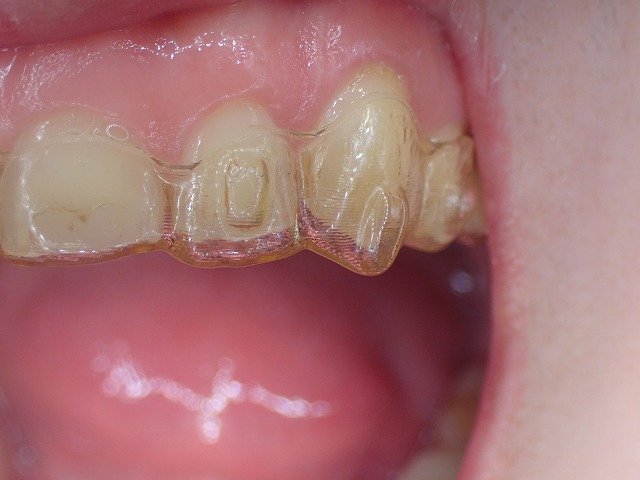

これが保定装置??なのか?? リテーナーにアタッチメント

アタッチメントは矯正途中につけるもの、矯正が終われば除去

マウスピースと、歯がきちんと適合していません。

マウスピースに凸状の形になった空間がありますが

これは、アライナーで歯を動かすために歯の表面に

「アタッチメント」を作ることがあります。

アタッチメントの跡があるということは

矯正中のアライねーでは?という疑問が残ります。

人工知能に聞い見ました。

これは想像ですが・・・

これはリテーナーではなくて、矯正途中のアライんだーだと

もしもそうならば、矯正途中に戻れ・・・ということです。